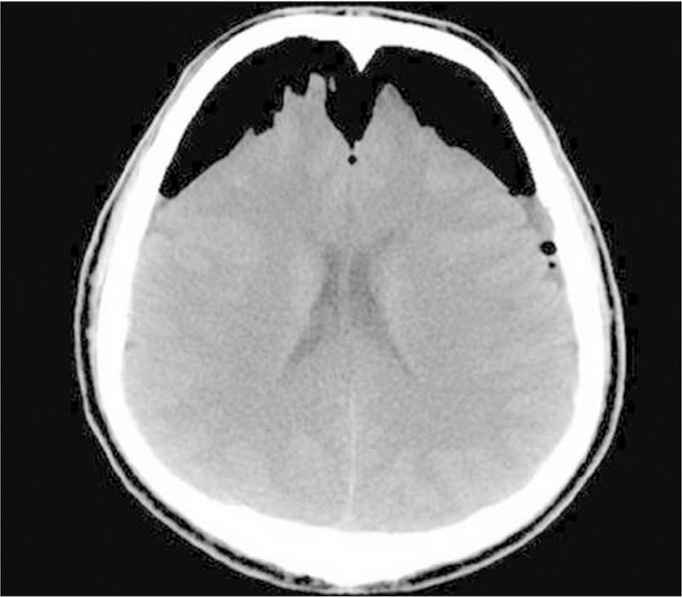

A 34-year-old gentleman presented to the emergency room complaining of sudden severe headache that started on the same day of his presentation. The headache was associated with frequent vomiting and clear fluid leakage from the left nostril. He had history of head trauma 3 months ago in another country, but did not require any surgical intervention as he claimed. Upon examination, he had normal vital signs. Results of his head examination revealed an old mild depression at the forehead region. His Glasgow Coma Scale (GCS) score was 15/15. Fortunately, his neurological examination was completely normal including the examination results of motor, sensory, cerebellar, and cranial nerves. His initial blood investigations were completely within the normal range. CAT scan was performed urgently and revealed a large area of encephalomalacia in the left frontal lobe filled with air, which communicated with the related frontal horn of the left lateral ventricle (Figure 1). A small defect was also seen in the posteroinferior aspect of the left frontal sinus, associated with multiple foci of PNC seen along the convexity of the brain, in the basal cisterns, and lateral and third ventricles as well. The CAT scan also showed an old depressed fracture of the left side of the frontal bone (depressed by 7.4 mm). Moreover, the volume of air in the intracranium cavity was estimated by the reporting neuroradiologist to be approximately 45 mL of air based on the patient’s CAT scan. The patient was urgently evaluated by the neurosurgical team and was taken on the same night for surgical repair. Accordingly, he underwent bifrontal craniotomy, repair of posterior sinus fracture, and recanalization of the frontal sinus. Postoperatively, he had an uneventful smooth recovery with rapid resolution of his headache. A repeat CAT scan of the brain was obtained and showed complete resolution of the PNC with small air foci noted in the right frontal horn of the lateral ventricle (Figure 2). On the 11th postoperative day, the patient was discharged home symptom-free.

Complete resolution of the pneumocephalus with small air foci noted in the right frontal horn of the lateral ventricle.